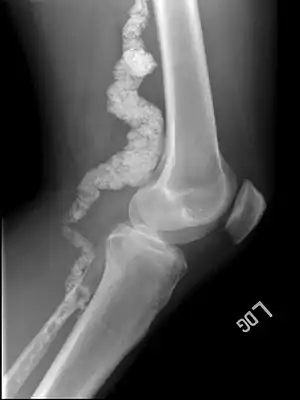

| A knee x-ray of a person with ACDC | |